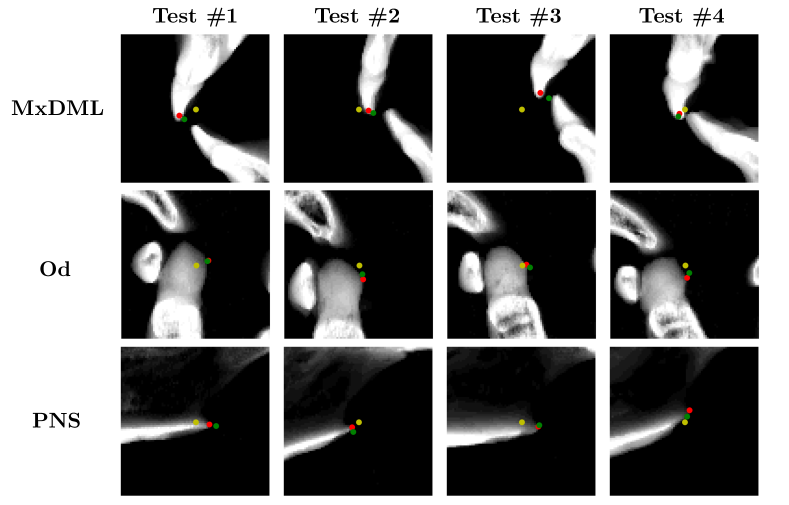

Landmarks on the cranium that demonstrates rigidity have less variability between subjects. According to [Yun2020], cranial landmarks have smaller variance compared to mandibular landmarks with the normalization presented in Section 2.1. Moreover, our empirical experiment shown in Figure 6 demonstrates that the rough local-to-global estimation achieved using the VAE-based low dimensional representation provides more accurate annotations for cranial landmarks. Therefore, we again utilize a VAE-based low dimensional representation in the same manner as in Section 2.2 by using only the cranial landmarks . To increase the detection accuracy, we enrich the partial knowledge of by accurately detecting three additional cranial landmarks lying near the midsagittal plane (MxDML, Od, and PNS) based on the rough estimation . The overall process is illustrated in Figure 5.

In Figure 9 and Table 2, qualitative and quantitative evaluations of the 2D CNN-based detection of three cranial landmarks on the midsagittal plane are provided. The detection achieved relatively accurate annotation on the three target landmarks.

| Landmark name | Initial error | 2D CNN error | Difference (mm) |

| MxDML | 2.76 | 1.42 | -1.34 |

| Od | 4.24 | 3.41 | -0.83 |

| PNS | 2.71 | 1.60 | -1.11 |